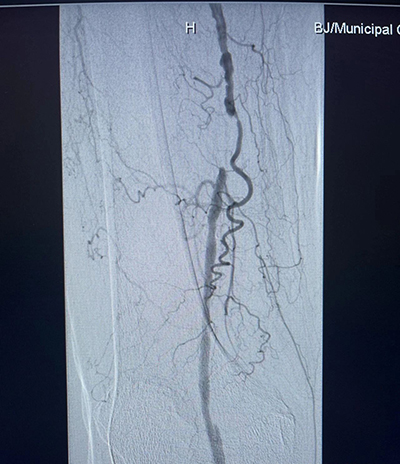

北京市垂杨柳医院介入与血管外科主任杨永久团队凭借丰富的经验和精湛的技术,为胡奶奶实施了微创手术。术前,团队进行了仔细的评估和周密的准备,确保手术的安全性和有效性。术中,他们通过微创手段在血管病变段放置球囊进行扩张,并植入支架,成功恢复了血管的通畅。这一手术的成功不仅让胡女士重新站了起来,更让她对未来充满了信心。同时,也展示了微创手术在超高龄患者下肢动脉治疗中的巨大潜力。